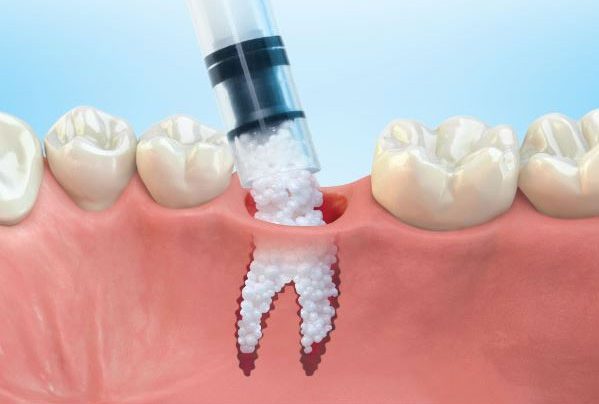

Bərpa texnikasının müəyyən edilməsi, sümüyün hansı bölgədə, hansı miqdarda itirilmiş olmasına bağlı olaraq müəyyənləşdirilir. Bərpa üçün tətbiq edilən sümük materialları pasiyentin öz donor bölgələrindən xüsusi metodlarla qazanılmış sümüklər, o cümlədən digər fərdlərdən alınmış və xüsusi qaydada hazırlanmış materiallar, heyvan mənşəli sümükəvəzləyici materiallar və sintetik materiallar olaraq ayrılır.

Bərpa zamanı yerinə görə bu materiallar ya ayrı-ayrılıqda, ya da kombinə olunmuş şəkildə tətbiq oluna bilir. Gündəlik təcrübədə həmçinin pasiyentdən götürülmüş qan nümunələrindən alınmış yüksək bərpaedici xassəyə malik materiallar (PRF) da uğurla tətbiq olunur. Sümükartırma metodlarının tətbiqi sayəsində, çənədə implantların yerləşdirilməsi üçün yetərsiz sümük həcmi olan bölgələrdə sümük miqdarı yetərli duruma gətirilir, uyğun boy və diametrə uyğun implantlar uğurla tətbiq olunur.